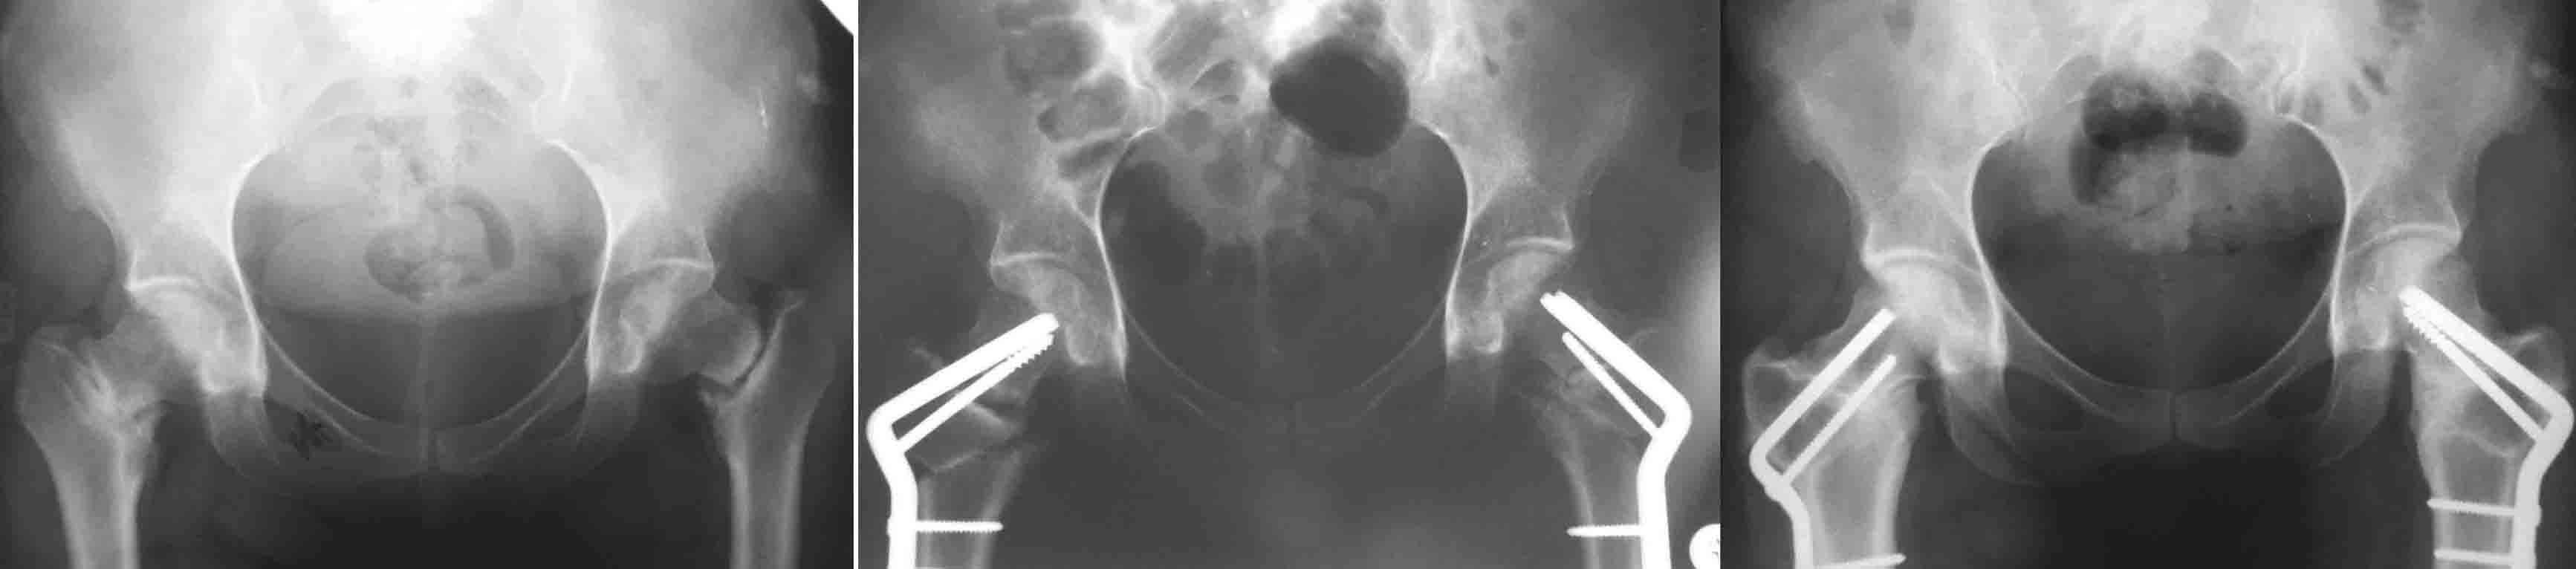

И клинковые и DHS, это всего лишь способ остеосинтеза, хотя, наверное, клинковые дают большую ротационную стабильность (по оси шейки), менее травматичны. Но это не постулат (1943 J Bone Joint Surg Am.;25:319-339. W. P. Blount BLADE-PLATE INTERNAL FIXATION FOR HIGH FEMORAL OSTEOTUMIES). При подвертельных остеотомиях с латерализацией клинковые пластины метод выбора (по другому латерализацию дистального не выполнишь). Оптимальними являються рассчеты СORA по Dror Paley (centr rotation and angulation). Взяты из книги Principles of Deformity Correction by Dror Paley. Для примера межвертельные при двусторонних ложных cуставах шеек.

Спасибо за статью. Может быть Вы имели в виду медиализацию, как на приложенных снимках? Так это от формы импланта зависит, так и пластину DHS можно изогнуть при желании (лучше тогда, наверное, брать DCS, чтобы нужный угол получить), а может быть они уже и есть такие где-нибудь у кого-нибудь.

Нет я имел в виду латерализацию.На приложенных снимках межвертельная остеотомия, т.е. уровень остеотомии близок к CORA, и ангуляция без трансляции (смещении по ширине латерализации) допустима: не будет происходить нарушение механической оси. В случае когда значительно укорочена шейка, большая разница в длине конечности и большая степень коррекции предпочтительнее подвертельная с латерализацией дистального фрагмента: функционально удлиняется шейка, большая коррекция длины конечности и нет натяжения m. Iliacus.